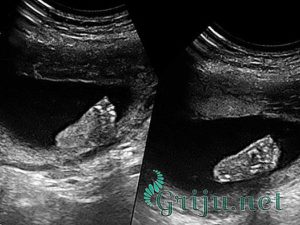

УЗИ

Обычно на 11 неделе беременности УЗИ пока еще не требуется. Но, в отдельных случаях – для подтверждения нормального протекания беременности, оценки развития плода и исключения возможных нарушений в развитии малыша или плаценты, для диагностики состояния матери при наличии ноющих болей в животе – женщину по решению врача могут направить на внеплановое ультразвуковое исследование.

Переживать будущей роженице не стоит – специалисты уверяют, что УЗИ является абсолютно безопасным методом обследования, а некоторых и вовсе обследуют при помощи ультразвука многим раньше, на 10, и даже на 9 неделе беременности.

Во время УЗИ врач сможет прослушать сердцебиение плода, и, исходя из полученных данных, сделать выводы о его развитии.

Также ультразвуковое исследование позволит врачу оценить размеры и состояние матки, установить место крепления плода и расположение плаценты, количество и качество околоплодных вод.

В целом, УЗИ будет еще одним «страховочным» методом выявления каких-либо патологий развития малыша и отклонений в протекании беременности вообще.

УЗИ на 11 недели беременности

Первое УЗИ на 11 недели беременности поможет будущей маме познакомиться с ребенком и его внутриутробной жизнью.

Некоторые женщины довольно критично относиться к УЗИ, но в настоящий момент доказано, что данный метод исследования наиболее безопасный для женщины и плода и способен определить возможные риски и развитие плода на любом этапе беременности.

Проводить УЗИ можно и раньше, но именно на 11 неделе беременности можно получить наиболее достоверные результаты в развитии плода, а также получить первое фото плода.

Помимо того, что данный вид обследования позволит определить развитие и рост плода – УЗИ 11 недели беременности поможет получить фото будущего ребенка. Если проводить УЗИ на современном оборудовании, можно получить не только фото, но и записать движение будущего ребенка на видео.

11 неделя беременности, размер плода, фото УЗИ достаточно четкое и часто позволяет будущем родителям осознать, что их в скором времени ждет пополнение.

Для врача УЗИ 11 недели беременности крайнее важное, поскольку благодаря ему можно убедиться, что плод развивается правильно и нет причины волноваться по поводу его развития. Если повезет, можно узнать и пол ребенка.